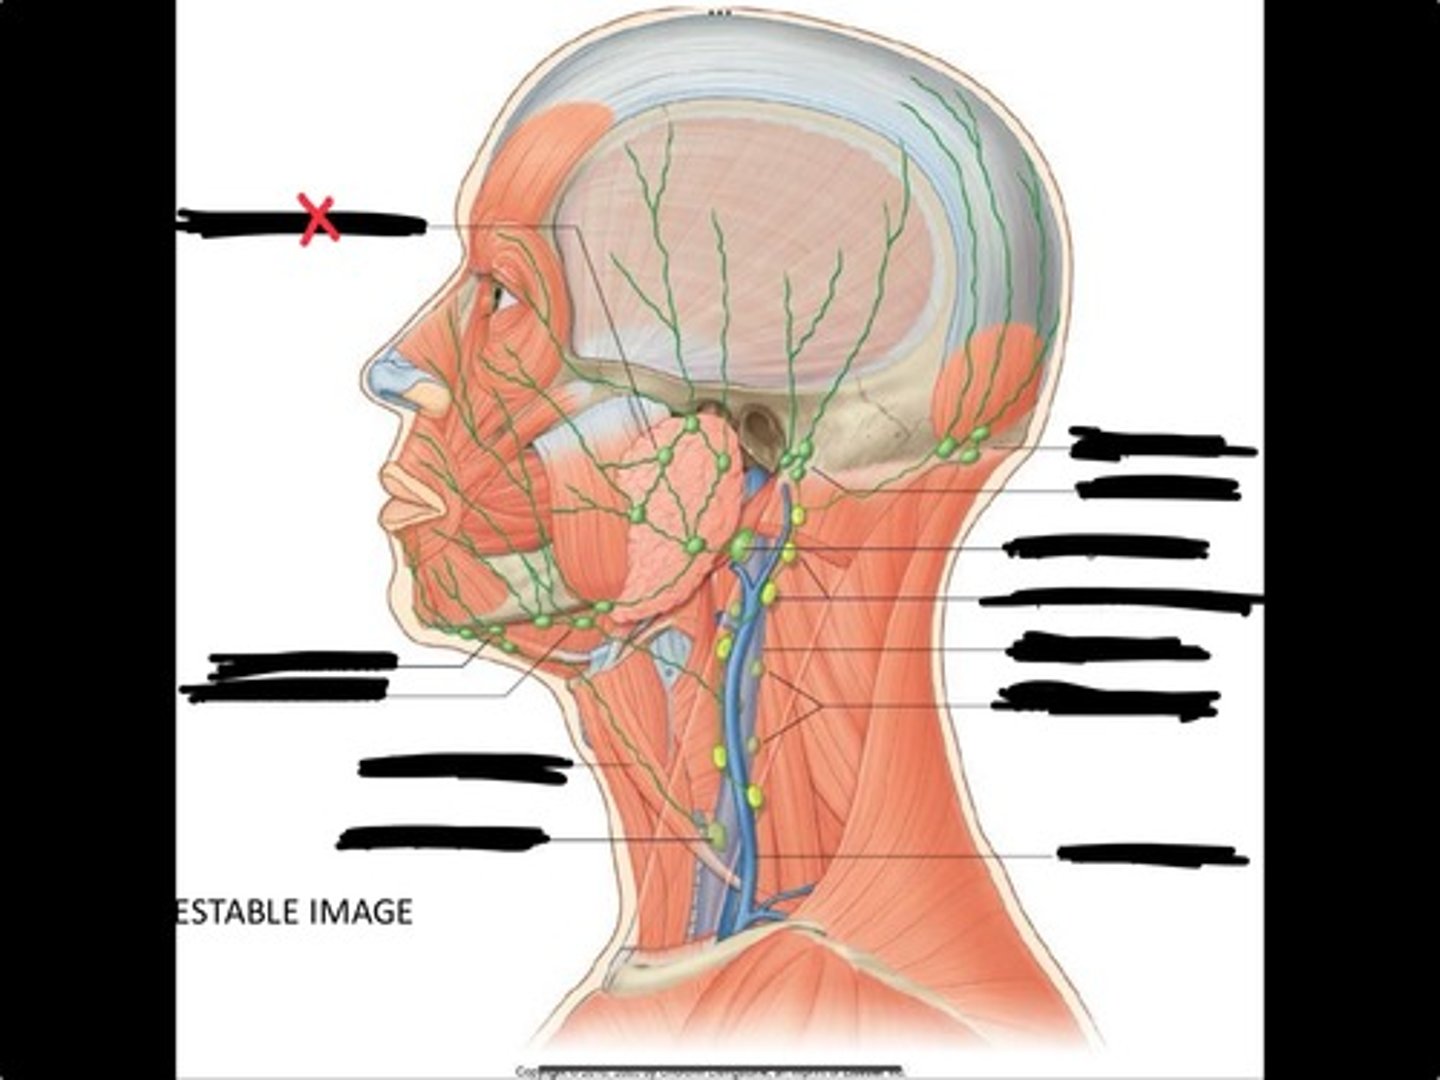

Jugulo-omohyoid node

Omohyoid muscle

Submandibular nodes

Submental nodes

Pre-articular/parotid nodes

Occipital nodes

Mastoid nodes

Jugulodigastric nodes

Superficial cervical nodes

Internal jugular vein

Deep cervical nodes

External jugular vein